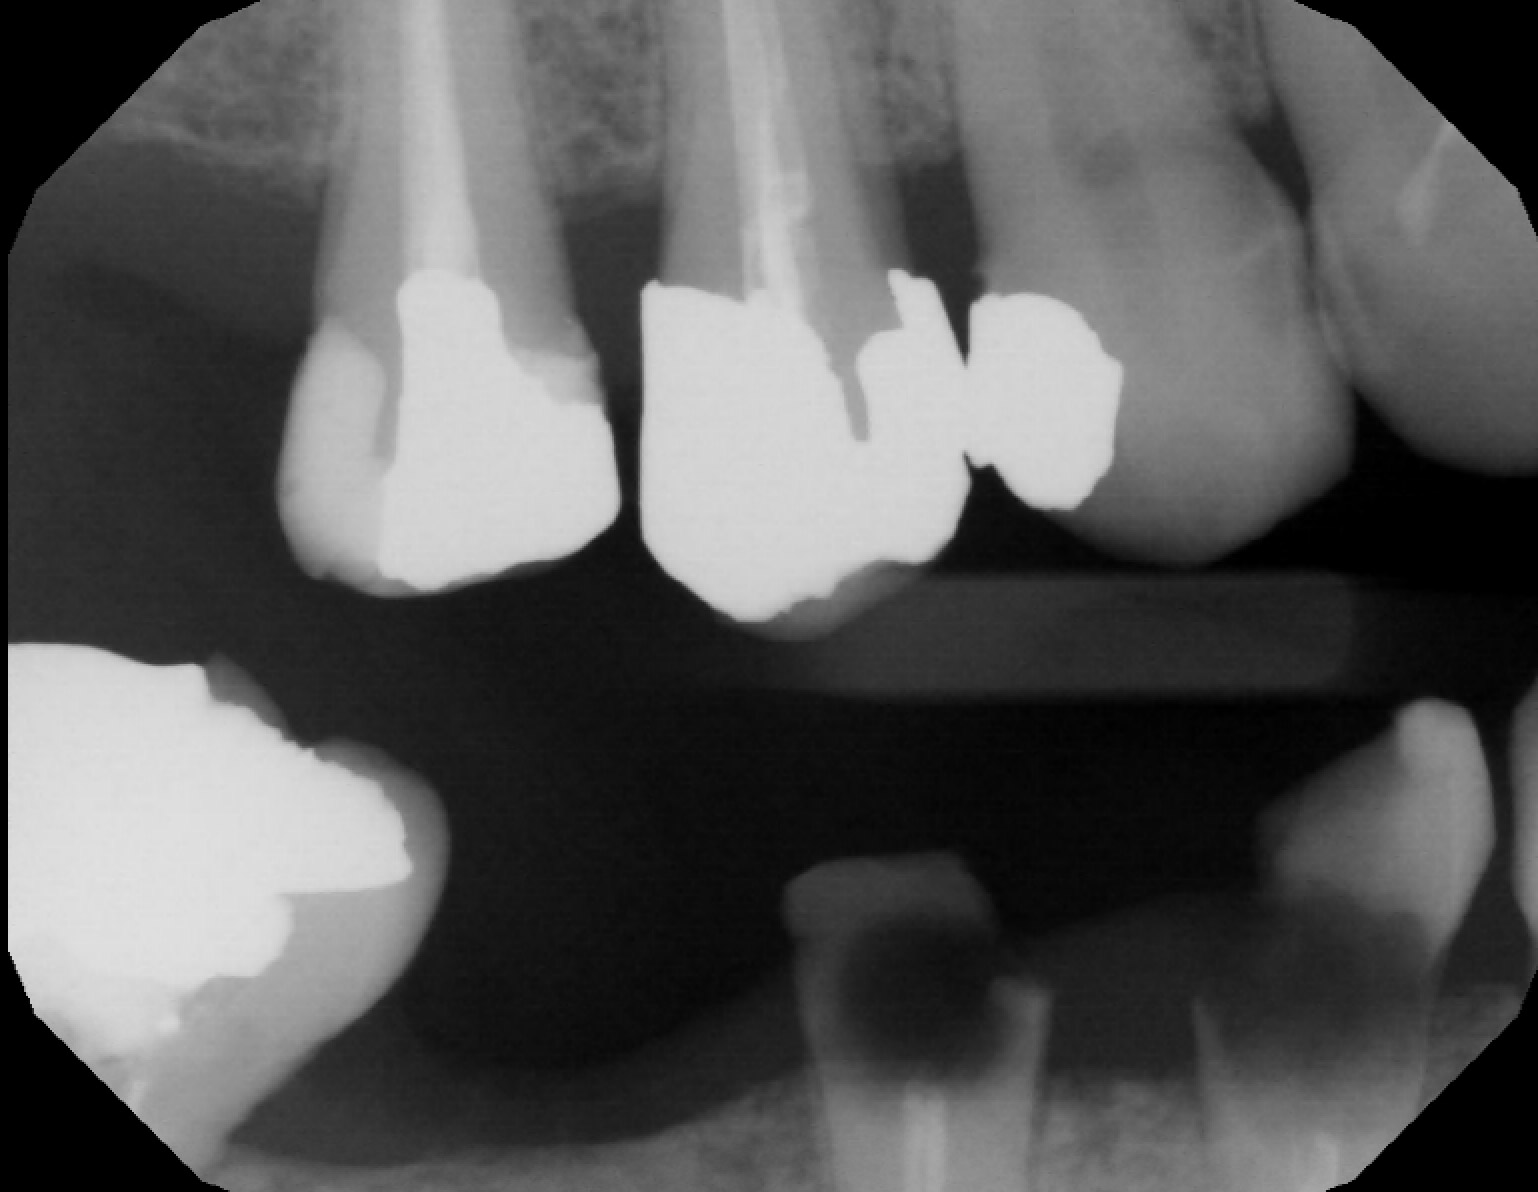

• Caries: 13 M (D) (US # 6), 12 D (D) (US # 7), 11 M (D) (US # 8), 21 M/D (D) (US # 9), 42 M (E) (US # 26), 43 M (E) (US # 27)

• Residual roots: 45 (US # 29). Fractured: 44 (US # 28).

• Endodontic fillings: 15, 14, 44, 45, 47* (US # 4, 5, 28, 29 and 31*)

• Periapical lesion on 11 (US # 8) and 21 (US # 9): correlates with the clinical finding of eroded teeth down to the dentin (almost the dentino-pulp junction)

• Note : The root canal on tooth 47 (US # 31) was done in Algeria and seems to have been an attempt. There is a broken instrument in one of the canals.